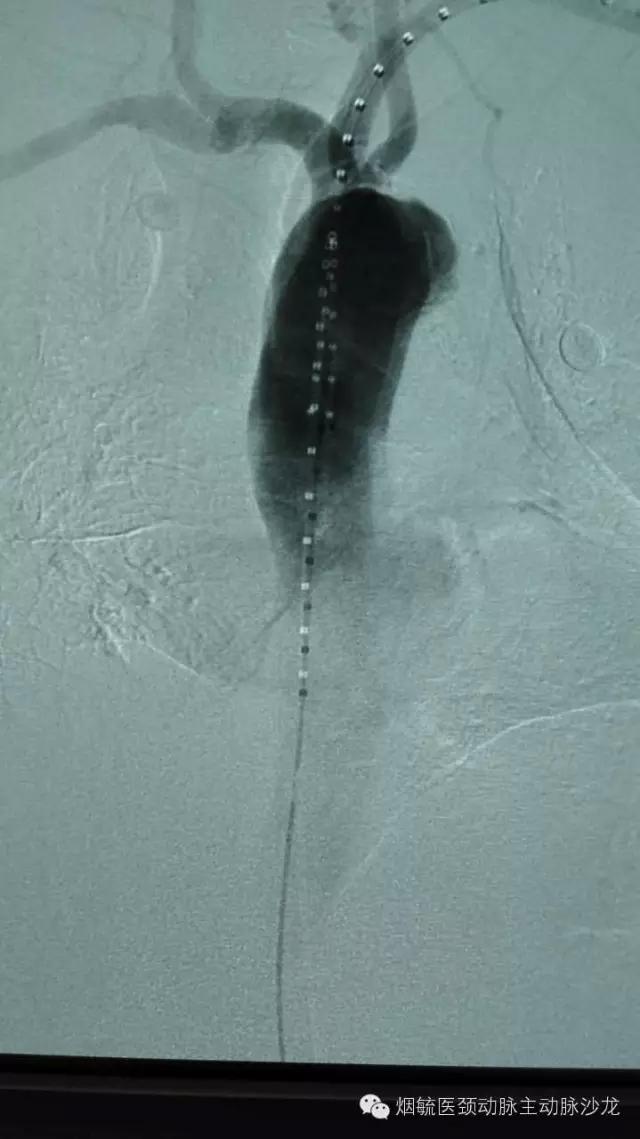

3天前60岁的王大爷前突然胸背部剧烈疼痛,疼到大汗淋漓,只能弯腰或屈膝卧床来缓解疼痛。在外院检查出胸主动脉穿透性溃疡合并璧间血肿,属于濒临破裂穿孔形成假性动脉瘤,必须立即手术,由于外院条件限制,家人带着王大爷来到烟台毓璜顶医院血管外科就诊。接诊的勇俊副主任医师为王大爷进行了紧急控制血压止痛等对症处理,并迅速策划科室专家会诊,讨论病情,制定手术方案,以杨牟教授为首的专家团队一致认为,手术刻不容缓,需紧急处理。在麻醉科及导管室工作人员的配合下,由张居文副主任医师带领的勇俊副主任医师、刘国龙主治医师和王涛住院医师组成血管外科动脉小组当天为患者实施了“胸主动脉腔内隔绝术+左锁骨下动脉烟囱置放手术”,手术顺利,患者转危为安。